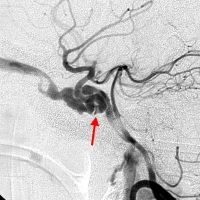

外傷性頸內動脈海綿竇瘺CT圖因此,常須採用股動脈插管行全腦選擇性血管造影 除了對患側頸內、頸外動脈造影之外,還要在壓迫患側頸動脈,暫時阻斷血流的情況下,拍攝對側頸內動脈和椎動脈造影像 通常在患側頸內動脈造影像上,只見海綿竇內一團造影劑陰影 遠端腦血管充盈較差 瘺口的確切部位難以確定。採用椎動脈造影同時壓迫患側頸動脈,使造影劑由後交通支逆行經頸內動脈海綿竇瘺口溢出,則往往清晰可見。同時行健側頸內動脈造影也可了解Willis環是否完整,估計腦動脈代償情況,有助於判斷患側頸內動脈血流是否可以中斷 另外,通過選擇性頸外動脈造影能顯示有無頸內動脈的分支與海綿竇底部腦膜中動脈、腦膜副動脈及咽升動脈相吻合,形成頸外動脈供血。Parkinson(1967)曾將外傷性頸內動脈海綿竇瘺分為兩類:其一,為海綿竇段頸內動脈本身破裂所致;其二,為海綿竇段頸內動脈的分支斷裂所引起。後者採用單純球囊栓塞常難以奏效。

腦血管造影可顯示頸內動脈、海綿竇、大腦中靜脈、蝶頂竇或眼靜脈明顯擴張。病側大腦前、大腦中動脈顯影不良。病變對側造影常顯示雙側大腦前及大腦中動脈充盈。